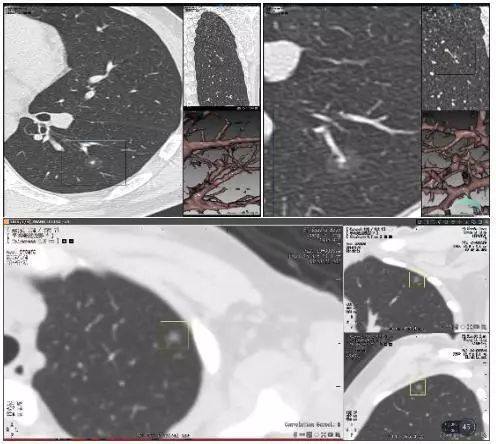

实性肺结节(solid nodule),间质血管都看不见(左上图),亚实性肺结节(subsolid nodule)包括纯磨玻璃结节(pure ground-class nodule,pGGN)(左下图),还有混杂性结节(mixed ground-glass nodule,mGGN),也称部分实性结节(part solid nodule),表现为间质样改变,中间实性,周围是磨玻璃样。

在2018年版的专家共识中,我们做了一个创新,首个共识提出大小分类:微小结节(直径<5mm),小结节(直径5-10 mm),肺结节(直径 30 mm以下)。这样分类有助于分级诊疗。

<5mm的微小结节对于病人来说,半年甚至一两年之内都没有很大的威胁,可以放心的在基层医院管理;

5-10 mm的小结节可以在有诊治经验的中国肺癌防治联盟肺结节诊治分中心管理;

≥10 mm的肺结节则应该尽早诊治,如果不能确诊,建议多学科会诊(MDT)。